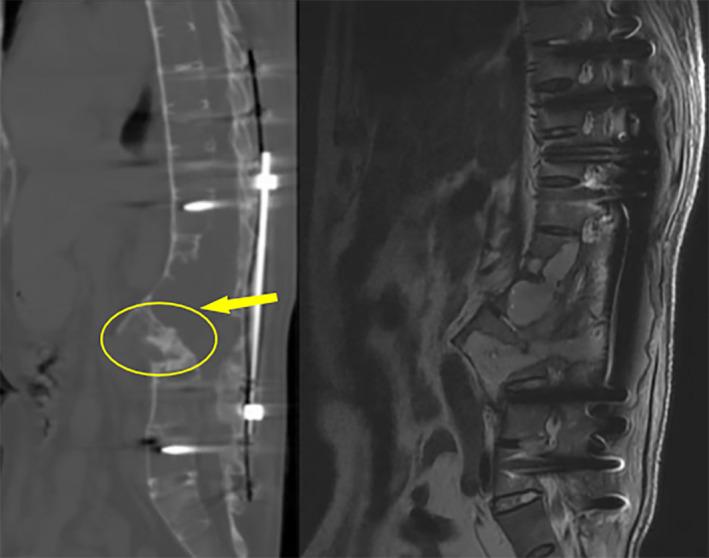

A 49-year-old male reported a 30-year history of thoracolumbar pain and limited mobility and was diagnosed with AS with dual complications of AL and ICSH. Before correction surgery, physical examination, x-ray, CT, MRI and Blood HLA-B27 examination were performed and a series of radiological parameters, including the degree of kyphosis and the T1-pelvic angle (TPA), were measured. Several days after surgery (Distal PSO was used), we performed examinations to check the patient's physical condition which showed the patient recovered remarkably. CTA was done, indicating that the patient's aorta moved anteriorly with the osteotomy side undamaged. A series of morphological parameters were measured again, including TPA, LL, and TK. CT and MRI were performed again, reflecting significant bone-to-bone fusion and successful recovery. The patient relieved the symptoms and regained his daily activities.

一名49岁男性有30年胸腰段疼痛及活动受限病史,被诊断为AS并伴有AL和ICSH双重并发症。在矫正手术前,进行了体格检查、X线、CT、MRI及血液HLA - B27检查,并测量了一系列放射学参数,包括后凸畸形程度和T1 - 骨盆角(TPA)。手术后几天(采用远端腰大肌松解术),我们进行检查以评估患者身体状况,结果显示患者恢复显著。进行了CT血管造影(CTA),表明患者的主动脉向前移动,截骨侧未受损。再次测量了一系列形态学参数,包括TPA、腰椎前凸(LL)和胸椎后凸(TK)。再次进行CT和MRI检查,显示有明显的骨对骨融合且恢复成功。患者症状缓解,恢复了日常活动。